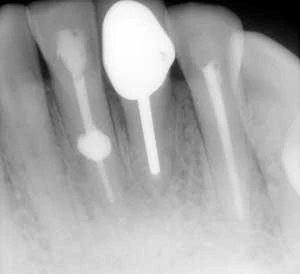

Phân biệt sự khác nhau giữa tổn thương nội tiêu và ngoại tiêu trên phim X-quang

Trong nha khoa không phải tất cả mọi thứ đều rõ ràng trắng đen, vẫn còn những vấn đề hóc…

Điều trị nội nha – tạo hình và làm sạch ống tủy có giải phẫu phức tạp ( phần 1)

Giải phẫu ống tủy và bản chất đa dạng của hệ thống tủy ở người là nguyên nhân của đa…